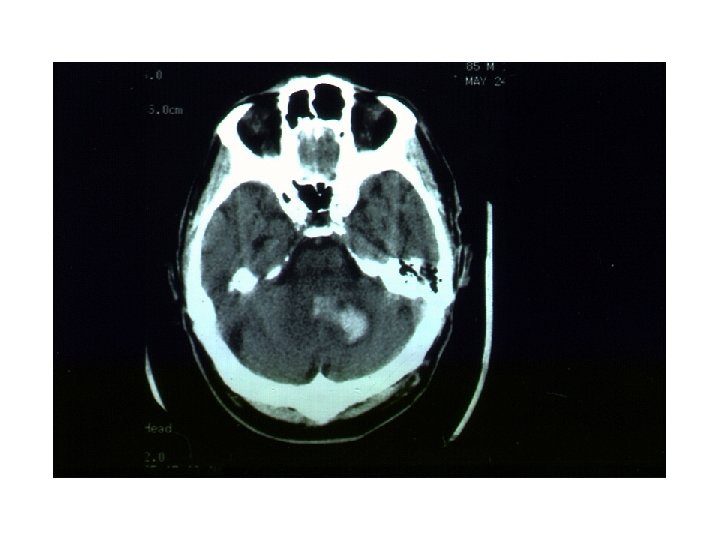

Spontaneous ICH in Taiwan, NTUH, 1993 • male/ female-- 1. 1/ 1 • prognosis-- 23 -30% death (24. 3% in patients with medical Tx. , 18. 7% in patients with medical & surgical Tx. ) • localization-- putamen 41%, thalamus 23%, combined p+t 9. 7%, subcortical area 9. 3%, brain stem 6. 5%, cerebellum 5. 9%

被殼出血 • • Flaccid hemiplegia Complete hemisensory deficit Homonymous hemianopsia Paralysis of conjugate gaze to the side opposite the lesion • Mild to moderate impairment of consciousness with or without headache and vomiting • Neuropsychological disorders (in some cases).

視丘出血 • similar syndromes may occur, but sensory deficit usually predominates over the other manifestations • Oculomotor signs such as forced downward gaze, convergence paralysis, and unreactive miotic pupils. • 被殼出血很大時,可以考慮手術,而視丘出血則 常常往下犯到腦幹,預後相當不好。一般比較不 考慮開刀。 • 另外,視丘非常靠近第三腦室。大部分的視丘出 血都會破到腦室裡面。這點比被殼出血常見。